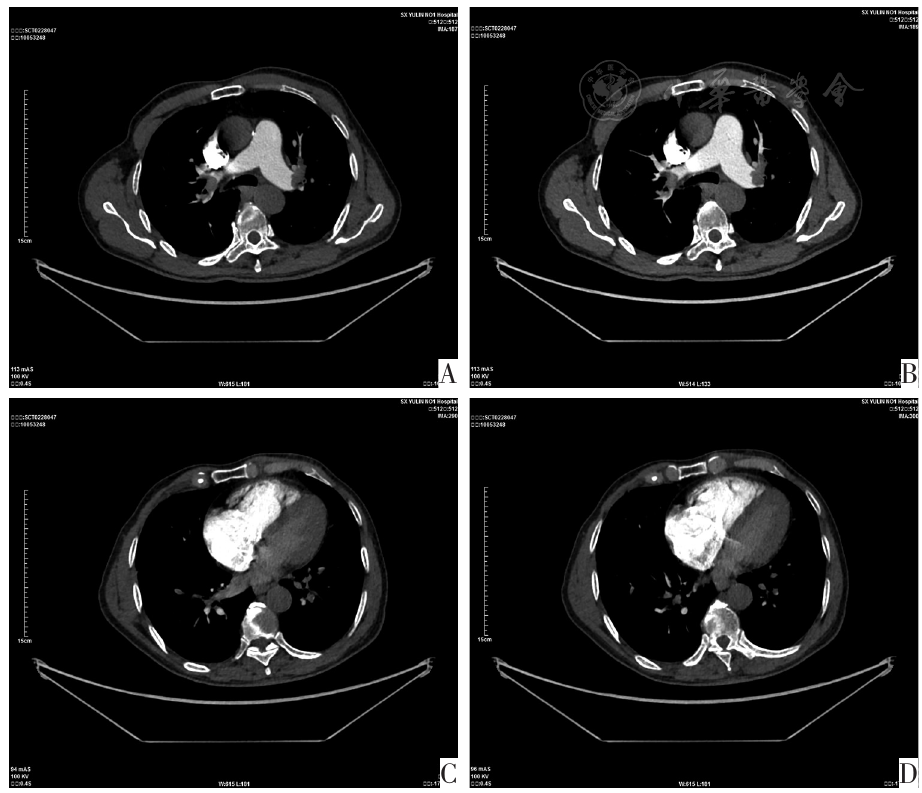

图1 典型病例的CTPA图像。图A、B为双侧肺动脉出现肺栓塞;图C、D为右心室和左心室测量显示右心室/左心室直径比为1.9,间隔向左弯曲进一步支持右室心肌应变